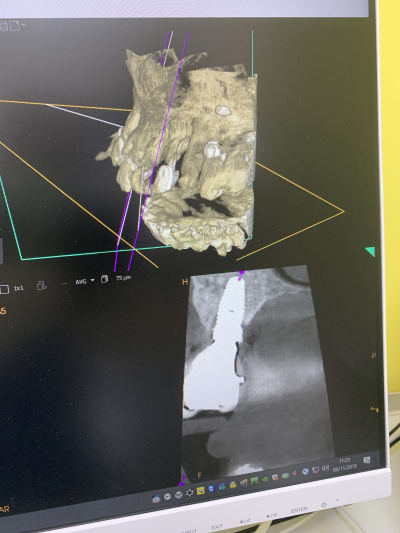

Il y a vraiment des différences de dingue entre les machines !

Les images 3 et 4, les images 6 et 7 sont prises à quelques années d’intervalles.

La machine de 2008 fait très peu d’artefacts, celle de 2018 énormément. Elle à le mar pour les « supprimer », mais ça n’arrange rien !

Les artefacts métalliques sont bien différents selon les machines.

A l’adf on me dit « regardez on voit même les spires des implants », avec ma bécanne de 2008 je vois les spires des vis dans les implants, les têtes de vis... je n’ai rien vu d’équivalent sur les machines récentes.

Les photos ne sont pas de très bonnes qualités, prises avec un 6S sans trop d’effort.

Regardez comme les tenons sont bien trop larges à la radio !

Les implants sont de gros pâtés blancs...